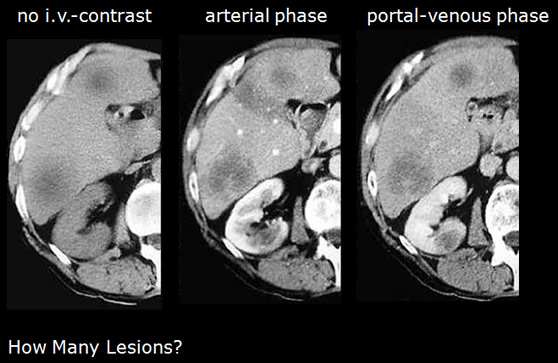

Importance of i.v.-contrast and proper timing, scanning delay